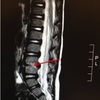

2

Homem, 15 anos, dor em região dorsal. Febre + tratamento para endocardite.

Espondilodiscite Redução do espaço discal, irregularidades dos platôs vertebrais adjacentes.